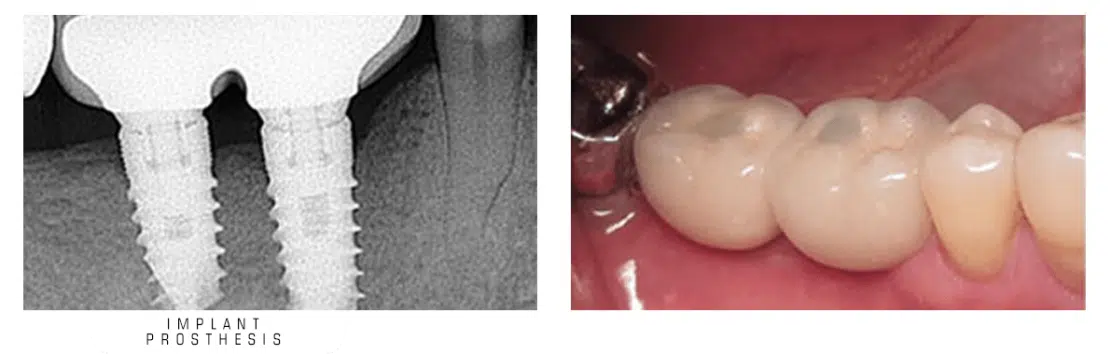

همانطور که در ابتدای مقاله عنوان شد، ایمپلنت دندان از سه بخش اصلی تشکیل شده که هر کدام نقش مهمی در جایگزینی دندان از دست رفته ایفا میکنند. پایه یا فیکسچر که شبیه یک پیچ کوچک است، درون استخوان فک قرار میگیرد و عملکردی مشابه ریشه دندان دارد و ثبات پروتز را فراهم میکند. روی فیکسچر قطعهای به نام اباتمنت نصب میشود که به عنوان رابطی بین پایه و پروتز عمل میکند و پروتز ایمپلنت را در جای خود نگه میدارد. پروتز که شامل روکش، بریج یا اوردنچر است، جایگزین تاج دندان یا دندانهای از دست رفته میشود و ظاهر طبیعی و عملکرد کامل دهان را بازمیگرداند. با کنار هم قرار گرفتن این سه بخش، ایمپلنت دندان امکان جویدن راحت، تکلم طبیعی و لبخندی زیبا را فراهم میکند.

برای بیمارانی که تنها یک دندان خود را از دست داده اند، از روکش دندان به عنوان پروتز ایمپلنت استفاده می شود. در واقع در چنین مواردی پس از جوش خوردن فیکسچر به استخوان فک، روکش دندان به عنوان پروتز روی آن نصب می شود. روکش ایمپلنت دندان ویژگی های تاج واقعی دندان را تقلید می کند و ظاهری طبیعی به طرح لبخند می بخشد.